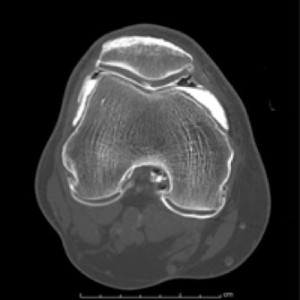

Tomografía computarizada Articulaciones o ArtroTC

Está indicado para el estudio mediante TC de articulaciones como el hombro, muñeca, cadera, rodilla, tobillo, etc., y es una alternativa cuando la artro RM está contraindicada.

Nos permite valorar lesiones de fibrocartílagos (meniscos), tendones, desgarros o distensión anormal de la cápsula articular, entre otras patologías.

Para la realización de esta técnica, se inyecta dentro de la articulación un medio de contraste. Este proceso se realiza con aguja fina y después de la aplicación de un anestésico local, por lo que se considera un procedimiento prácticamente indoloro.

Ejemplos